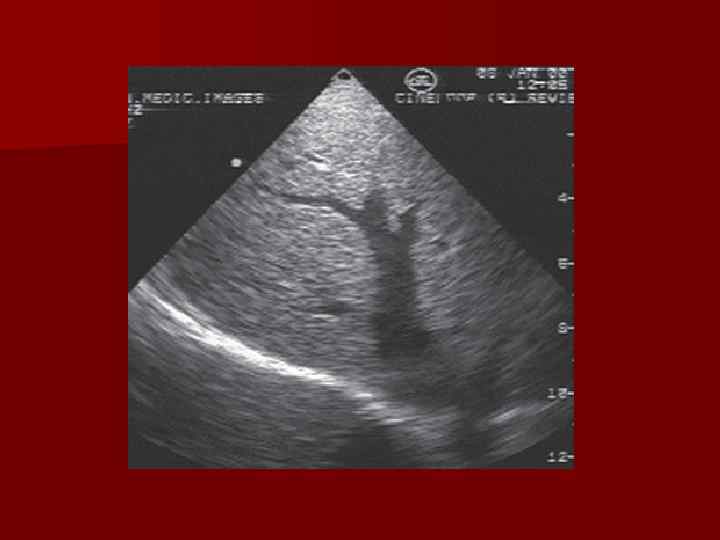

Кровеносные сосуды n Ветвление воротной вены n Ветвление печеночной артерии n Ветвление печеночных вен Кровеносные сосуды n Ветвление воротной вены n Ветвление печеночной артерии n Ветвление печеночных вен

Печеночные вены n Кровь из печени оттекает по печеночным венам (добавочная, правая, средняя и Печеночные вены n Кровь из печени оттекает по печеночным венам (добавочная, правая, средняя и левая, а также более мелкие), от соответствующих долей к каудальной полой вене n Возможна вариабельность слияния вен n С левой стороны полая вена имеет мешкообразное расширение